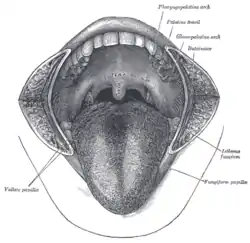

Soft palate without tonsils (after tonsillectomy)

Sagittal section of nose mouth, pharynx, and larynx. The mouth cavity. The cheeks have been slit transversely and the tongue pulled forward.

The mouth cavity. The cheeks have been slit transversely and the tongue pulled forward. Lateral wall of nasal cavity. (Soft palate visible in lower right)